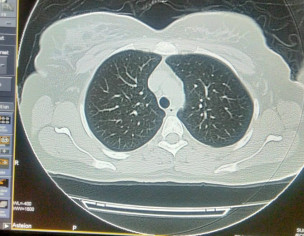

Plz describe it. Film of hrct of corona patient

plz contact radiologist